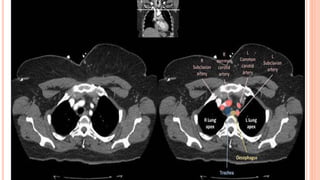

CT at level of Carina

CT at levelof Carina